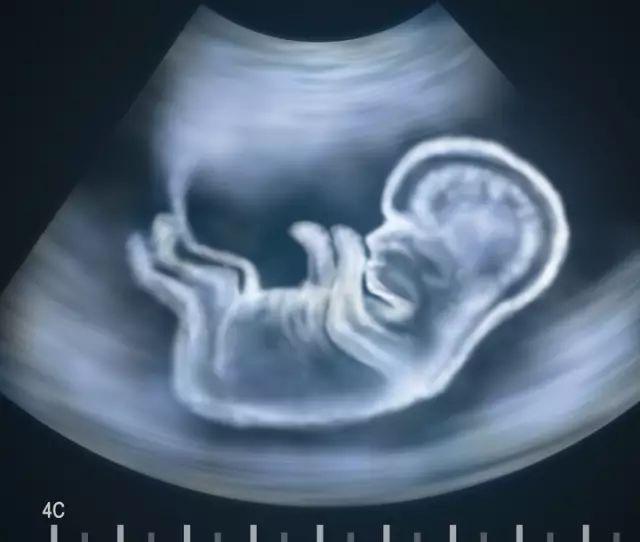

【诊断:孩子出生竟然没眼睛!这8种胎儿缺陷B超查不出来产检都正常】怀胎十月的刘女士终于迎来了自己的儿子小明 。 但是 , 新生命诞生的喜悦感并未持续太久 。 家人带着小明去医院的眼科检查 , 医生的回答令他们颇受打击 。

无眼症是一种罕见的疾病 , 发病率非常低 ,一些患儿部分缺少眼球组织 , 而一些患儿则是彻底没有任何眼球组织 , 这种畸形疾病很难通过B超检查提前发现 。

因为有些异常 , 是现阶段的产检B超发现不了的 。 另外 , 几乎所有胎儿的内脏器官 , 在出生前都会持续不断的成长变化 , 因此并非在早期检查时 , 为正常状况的器官 , 就能保证在出生后也一定正常 。

虽然B超不是万能的 ,但通过B超检查 , 绝大部分常见的异常都可以及时被揪出来 , 所以 , 不要因为B超不完美而放弃做B超 。

下面就来介绍一下 , B超可能发现不了的8种缺陷 。